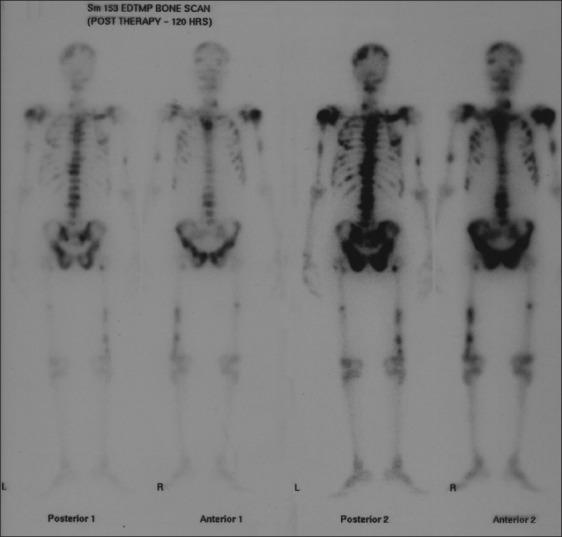

A 72-year-old male, a known case of carcinoma of prostate, had bilateral orchidectomy in 2002 and while on hormones developed multiple bone metastases in 2010. He was treated with (153)Samarium ethylene diamine tetra methylene phosphonate (EDTMP). The author compares the features of (99m)Tc methylene diphosphonate (MDP) scan and (153)Sm EDTMP bone scan, highlighting the similarities of skeletal uptake.